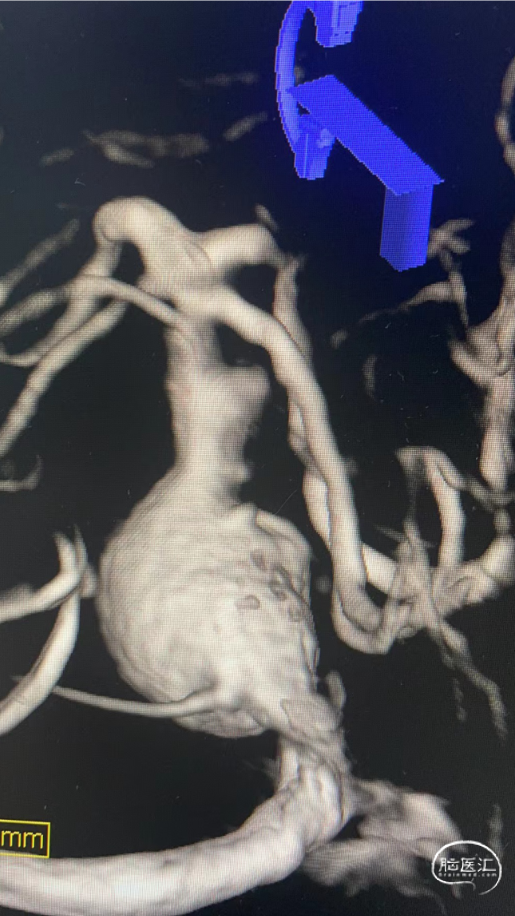

术前影像资料

术前测量:

覆盖长度:37mm

动脉瘤内有血栓,部分不显影。

直径:

瘤颈远端:3.83mm

瘤颈近端:4.71mm

近端锚定点:3.73mm

选择Lattice血流导向密网支架

5.3mm*37mm,8个球囊